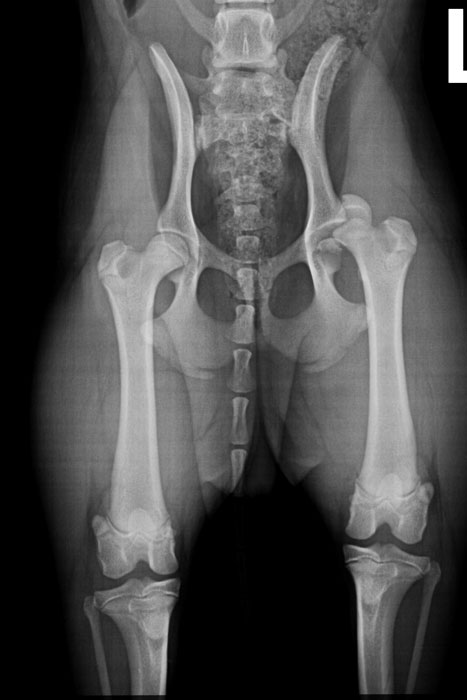

Schöner Rekord in der Tierklinik Ismaning: Chefchirurg Dr. Klaus Zahn hat vor Kurzem die 70. Mikrohüfte implantiert. Als einer der wenigen Spezialisten in Deutschland verfügt der Orthopäde über das nötige Know-How im Umgang mit den Mini-Implantaten, um auch kleine Hunde und Katzen prothetisch versorgen zu können. Patient Nr. 70 war die gerade mal sieben Kilo schwere Jana. Der Jagdterrier war beim Gassigehen über die Felder geprescht und auf drei Beinen humpelnd zurückgekommen. „Wahrscheinlich ist Jana beim Rennen irgendwo hängengeblieben“, vermutet ihr Halter. Auf jeden Fall hatte sich der Welpe die linke Hüfte ausgerenkt, wobei auch noch der Oberschenkelkopf in drei Teile zerbrochen war. Durch das künstliche Hüftgelenk wird das sieben Monate alte Tier trotz der Schwere der Verletzung aber ein aktives und schmerzfreies Leben führen können. Schon drei Wochen nach der OP hatte ihr Halter alle Mühe den Welpen ruhig zu halten. Froh ist er über das wöchentliche Training auf dem Unterwasserlauf, das die Tierklinik anbietet. „Das dient der Reha und lastet Jana auch aus.“